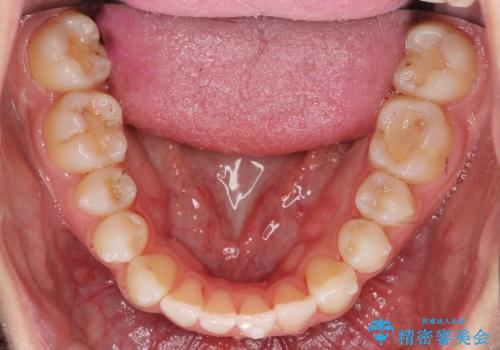

- 前歯のがたつきと小さな歯の形を治したいと来院。

前から2番目の歯が小さく、細くとがった形になっていました。

大きくしようにも、幅が少ない上に、また、内側に入ってしまっているため、矯正治療で前歯を並べてからセラミックでかぶせることにしました。

先に矯正治療をすることで、下の前歯を内側に入れることができ、上の歯のセラミックの幅や厚みを取ることができました。